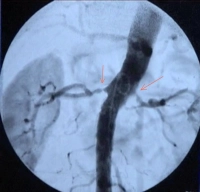

Perioperative - Perkutane transluminale Angioplastie mit Stentimplantation - Perkutane transluminale Angioplastie mit Stentimplantation bei Nierenarterienstenose bds.

• hochgradige Nierenarterienstenose (> 70 %) einseitig oder beidseitig mit dem Ziel des Organerhalts (Indikation im Filmbeispiel)